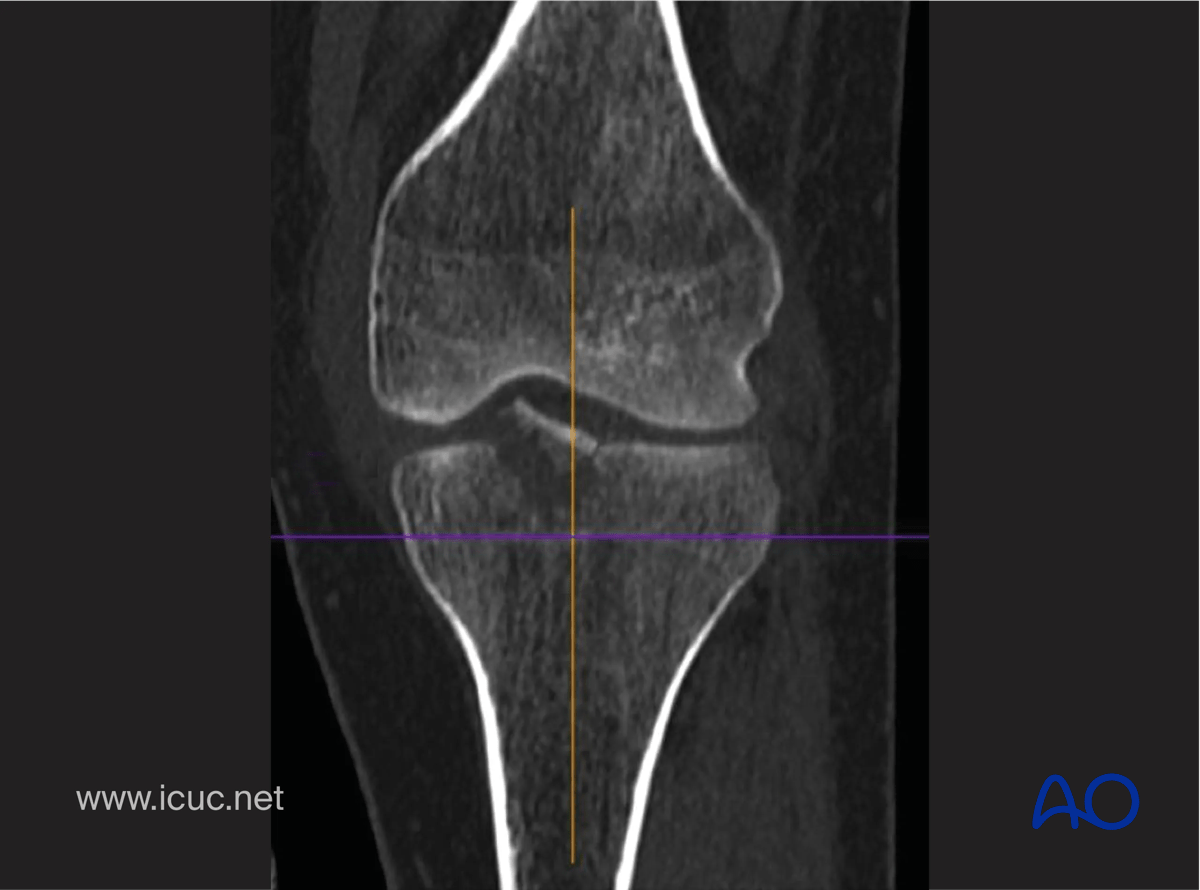

CT scan in coronal image showing the displacement.

CT scan in coronal image showing displacement of tibial spine